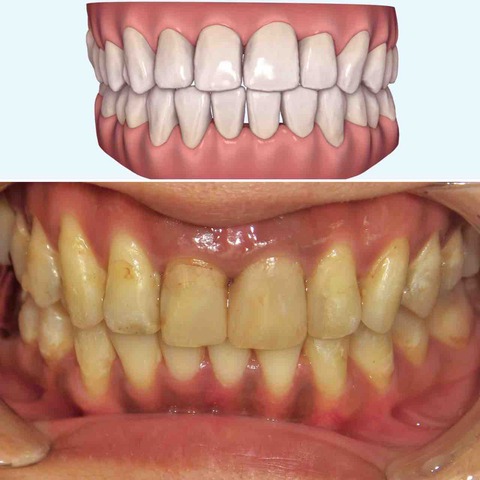

インビザラインで治療を終了した10代の患者さんのケースをご紹介する。

2024年4月5日に治療をスタートした。

内側に引っ込んだ歯を治したいという希望だった。

横から見ると少し前歯が出っ歯気味になっている。

2025年1月5日 わずか9か月後の状態。

横からは、やや出っ歯だったのが、出っ歯感はなくなった。